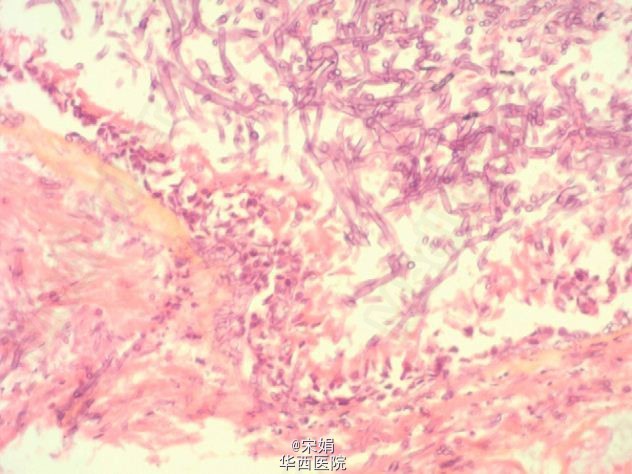

患者 55 岁男性,既往有糖尿病和慢阻肺病史,予吸入激素治疗后,出现了肺炎军团菌性肺炎,伴严重低氧血症。入院第 2 天,因多器官功能衰竭,转入 ICU 治疗。入院第 5 天,常规的辅助通气已不能维持生命体征稳定,加用体外膜肺氧合支持治疗。入院第 6 天,行纤支镜检查见支气管粘膜发生严重的炎性改变、溃疡、坏死和假瘤样病变。

纤支镜活检标本病理学提示:侵袭性气管支气管曲霉病。